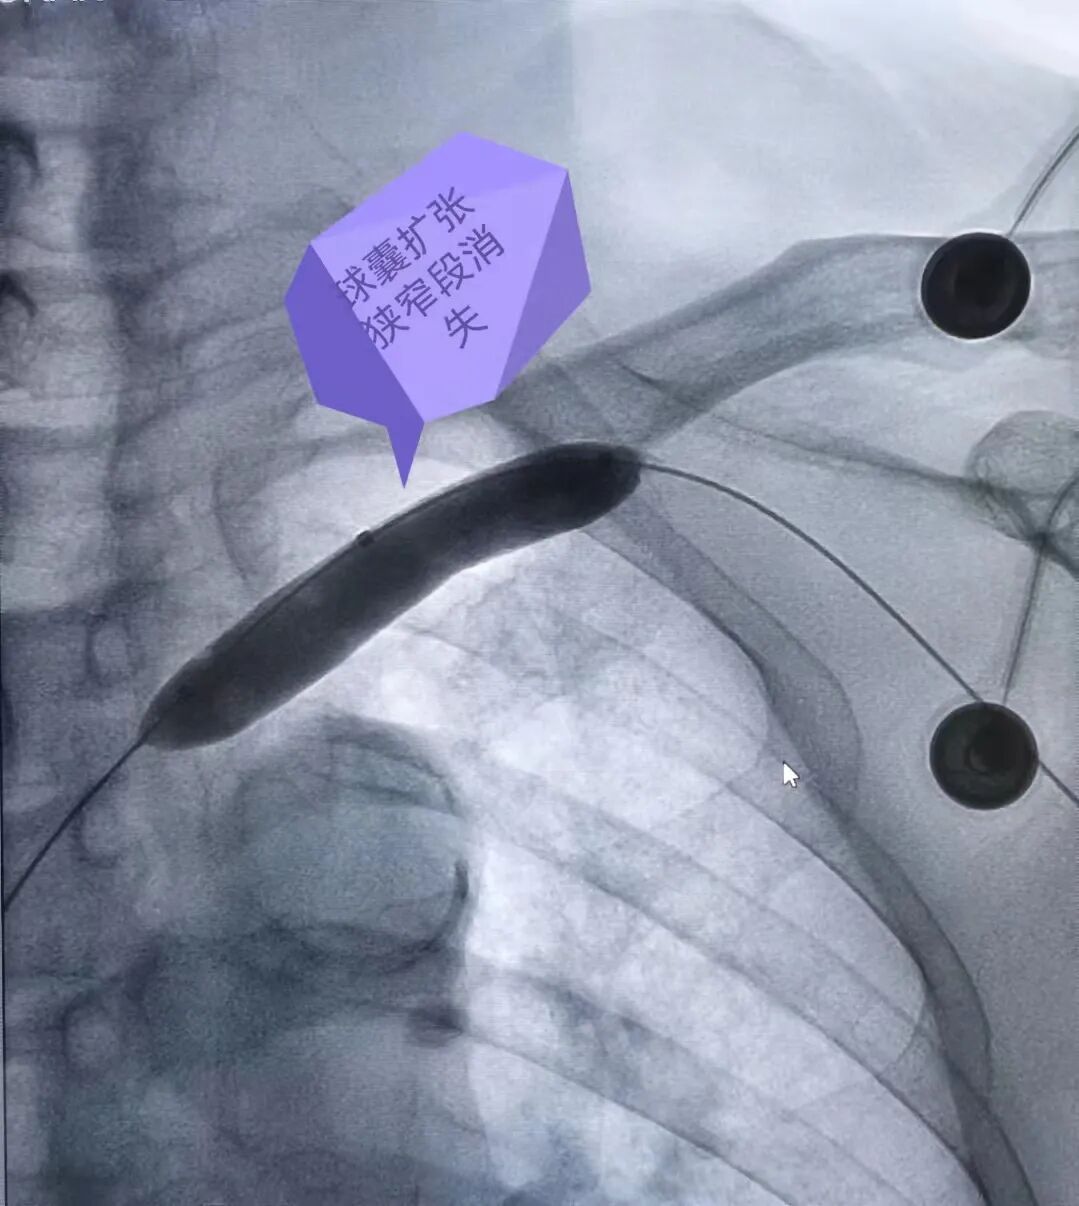

下面由我们介入中心的杨帆主任快问快答给大家做个简单的科普吧! 问:杨主任,只是做个透析嘛,怎么会手肿胀呢? 杨主任:球囊扩张是肿胀手的首选,不需要放支架,因为支架置入易使远期并发症明显增加。那么,哪些情况应该植入支架呢?我们可以根据球囊扩张后复发的时间来确定,通常采用3个月为期限,如果三个月内复发,可以植入支架,否则,应该行重复性球囊扩张,每3-4个月扩一次,我们将这种方式叫“维护性球囊扩张”。